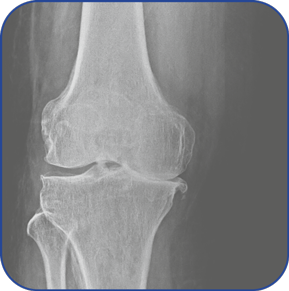

Knee Structure is complex.

Knee Pain (Early Arthritis) begins around age 40 and goes ignored till knee erosion reaches Grade 4 (last level) Arthritis that reduces mobility, brings lifestyle compromises & demands surgery.

Knee Pain, Early Arthritis

xray

Free X-ray Assessment

through AI